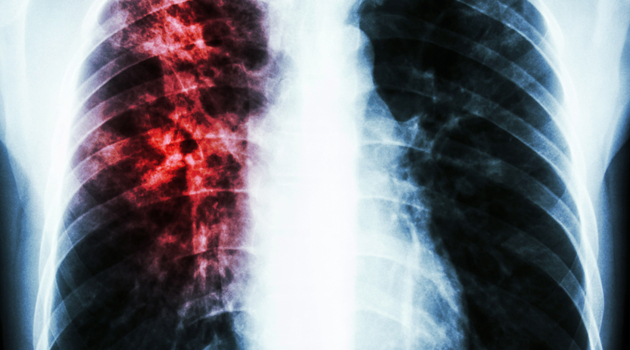

Как определить туберкулез на ранней стадии

Врач рассказала, что пандемия короновируса снизила риск заболевания туберкулезом